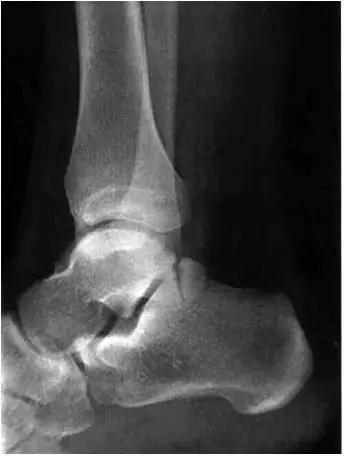

男,11岁,自述后踝下方疼痛,活动时为甚,并有一突起。

- 踝关节正侧位X 线平片,侧位片均显示距骨后方有三角形或椭圆形的距后三角骨。部分病例伴有轻度的踝关节骨性关节病。

- MRI 检查示距后三角骨及周围软组织有水肿信号,距后三角骨和距骨之间正常的低信号纤维连接中断,出现液性信号。